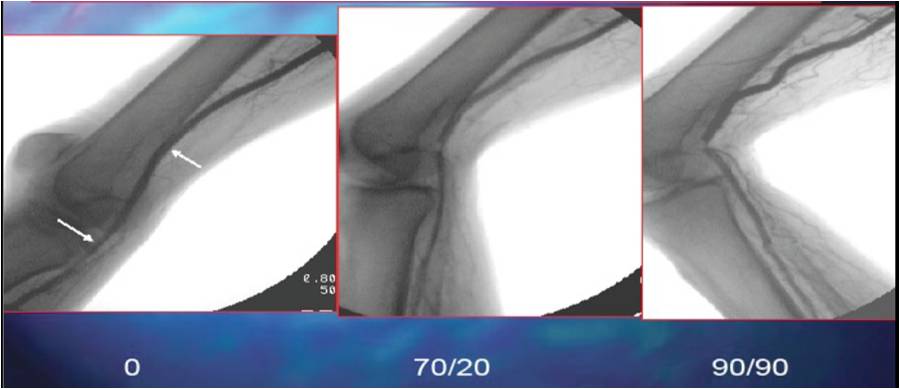

Popliteal kinking is theorized as one of the causes of stent failure in the popliteal space. In an interesting study of 68 patients undergoing angiography of the popliteal artery, a hinge point was identified in 98.6{8ceaa46882e4d49283ff23b35262537230ad541262f55a031ead545e66522058} of patients (Diaz et al. (1), See figure 1).

Because of the intrinsic movement of the knee joint and generation of a hinge point, use of PTA alone, self expanding stents with crush-resistant properties and endovascular stent grafts have been widely studied. The average patency rate of the popliteal artery after PTA alone is approximately 47{8ceaa46882e4d49283ff23b35262537230ad541262f55a031ead545e66522058} at 2 years. The longer the lesion length, the higher the restenosis rates. (reference 1, reference 2, reference 3).